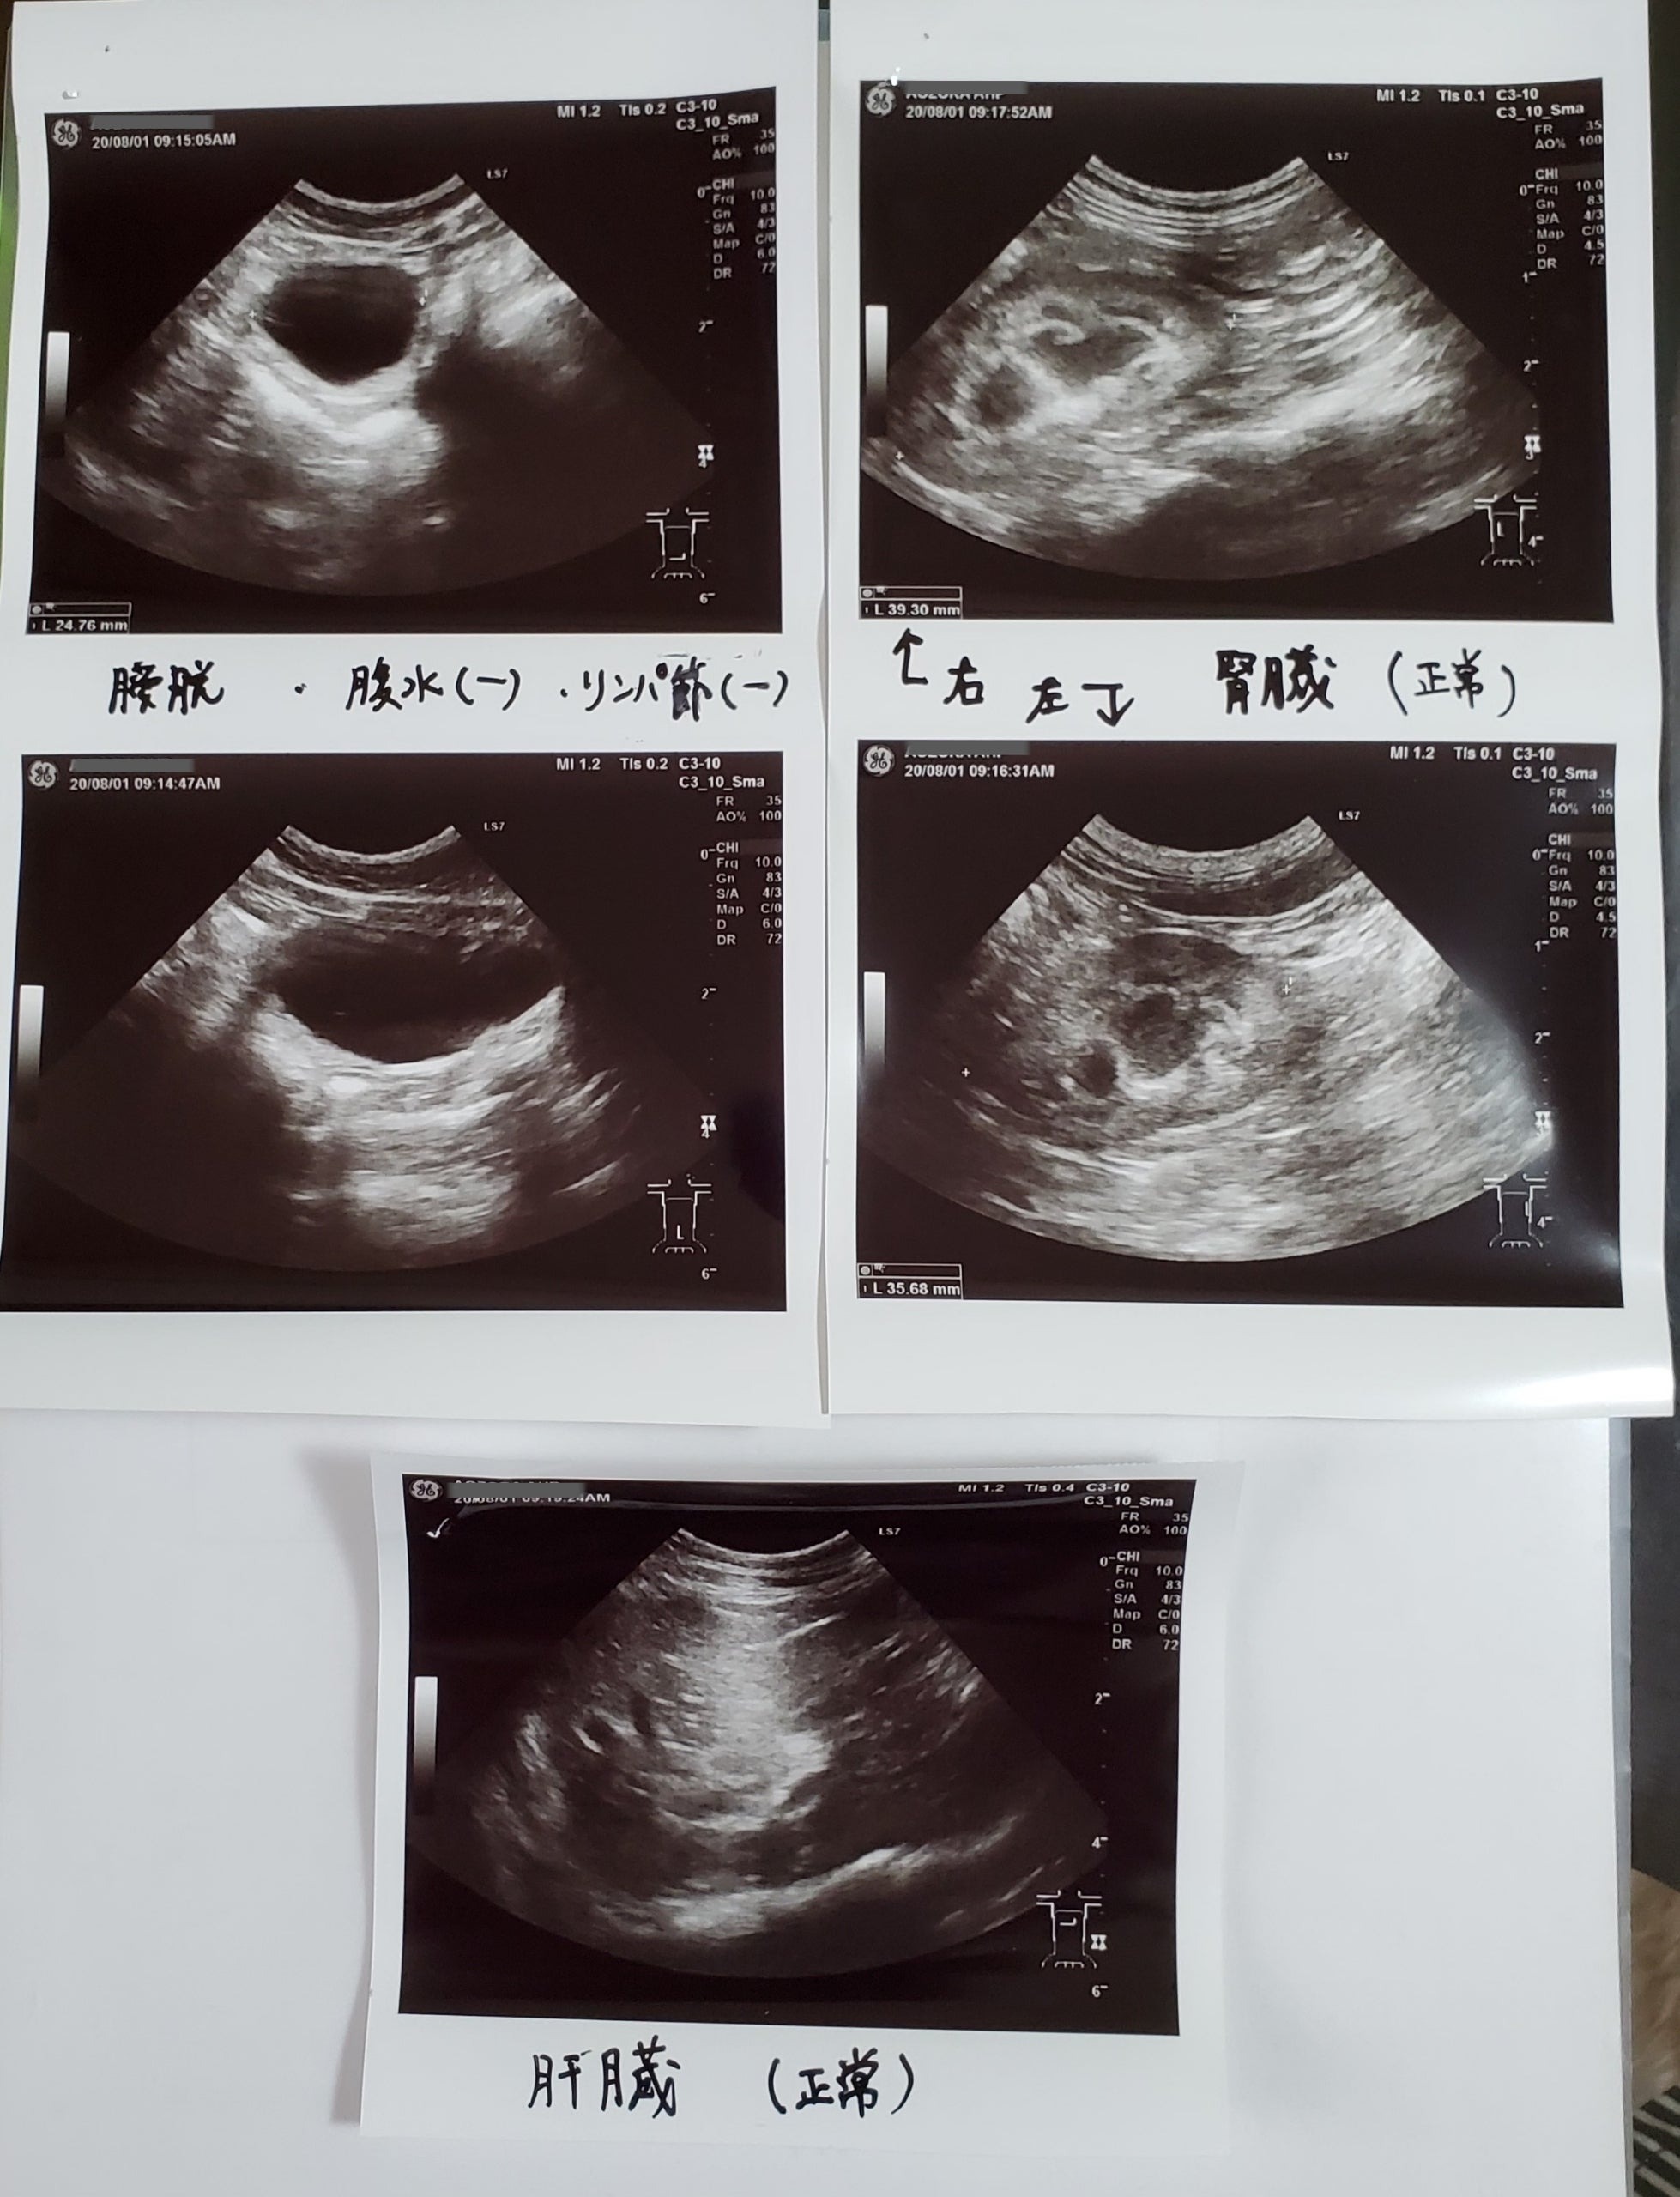

スクリーニング エコー検査も

肝臓、膀胱(前は肉芽腫あり)も大丈夫でした。